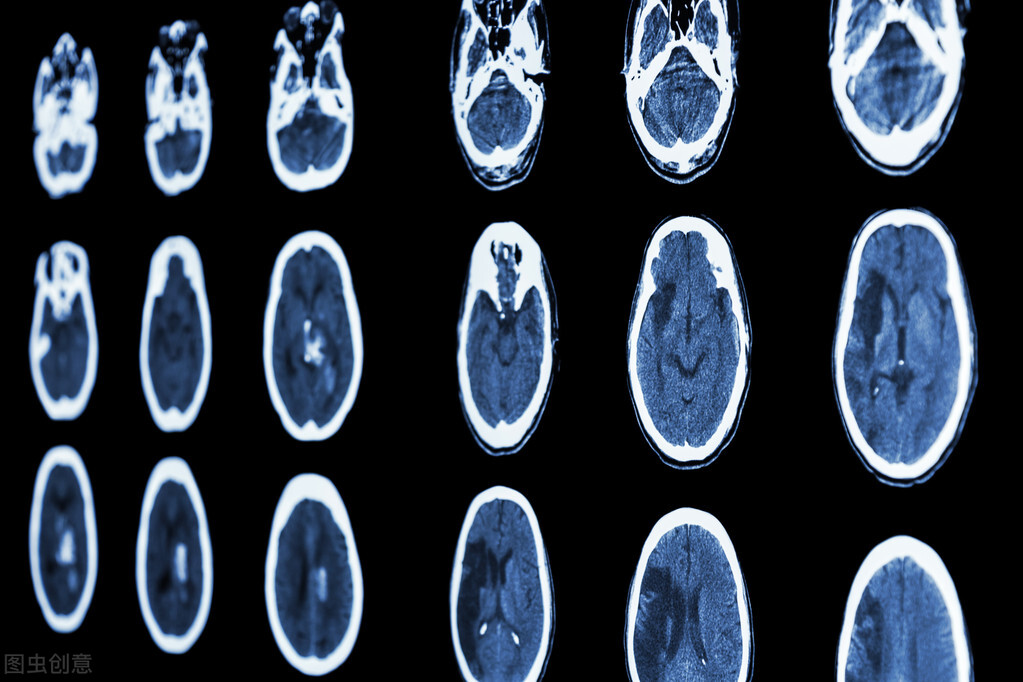

在我国脑卒中的人越来越多了,无论是出血性的脑出血,还是缺血性的脑梗死,都属于脑卒中的范畴。

不过在所有脑中风患者当中,最常见的其实就是脑梗死了,有80%的患者都是这个问题。

中风其实是很可怕的一件事,因为它的发病率很高,而且死亡率和致残率也都不低。

但是我们国家的脑梗死发病率可能会更高,这可不单单是肥胖导致的,因为脑梗死的发病和很多因素都有关。